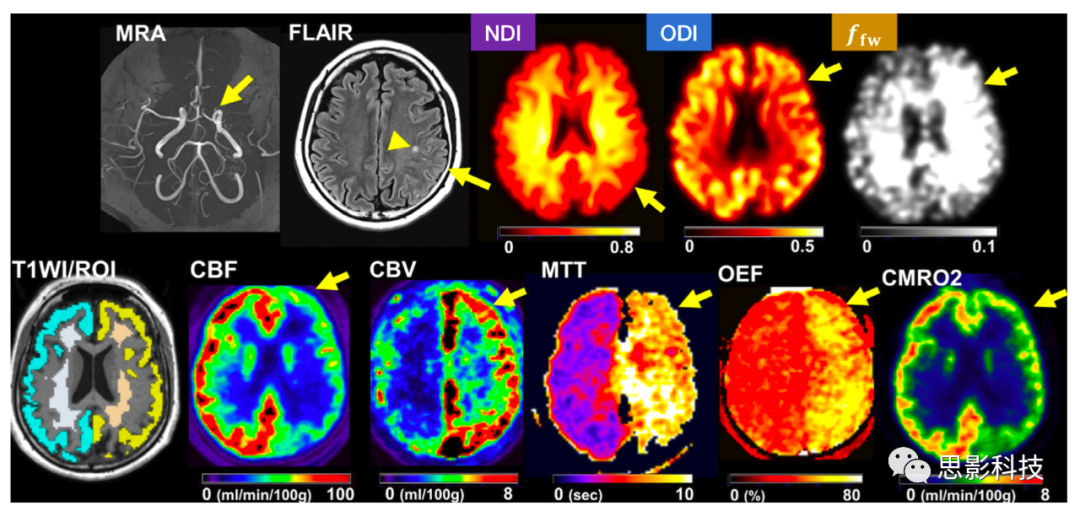

煙霧病(一種以Willis環(huán)進(jìn)行性閉塞為特征的疾病)患者中,GMWM中的NODDI參數(shù)與采用15O-gas PET測(cè)量的血流動(dòng)力學(xué)活動(dòng)及神經(jīng)認(rèn)知障礙相關(guān),提示NODDI對(duì)慢性缺血所造成的損傷是敏感的(圖6)。NDIODI降低,ffw增加與更嚴(yán)重的缺血性負(fù)擔(dān)和認(rèn)知障礙有關(guān)??偟膩?lái)說(shuō),盡管模型假設(shè)的有效性存在爭(zhēng)議,尤其是在急性期,NODDI已顯示出追蹤由缺血引起的腦改變的能力,且它對(duì)于預(yù)測(cè)慢性殘疾的具有潛在價(jià)值。

6. 煙霧病的NODDI研究

同側(cè)大腦動(dòng)脈狹窄時(shí),NDI、ODI降低,ffw升高,同時(shí)腦血流量(CBF)、腦氧代謝比(CMERO2)降低,腦血容量(CBV)、平均運(yùn)輸時(shí)間(MTT)、氧提取分?jǐn)?shù)(OEF)升高(箭頭)。